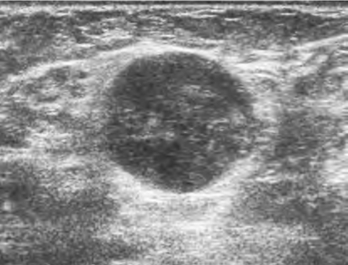

1.典型乳腺癌声像图特点(图8-5)

(1)边界不清,表面凹凸不平,无包膜。

(2)纵横比>1,形态不规则,前后径大于左右径,常呈蟹足形,星芒形,煤块形。

(3)回声比大,癌肿内部回声极低,与周边组织强回声形成明显差异。

(4)后方回声衰减,无侧方声影。

(5)视触比大,癌肿向周围组织浸润,触诊大小和超声所见实际癌肿大小差异较大。

(6)同侧腋窝淋巴结肿大,部分病例可以出现同侧锁骨上、下及颈部淋巴结肿大。转移性癌性的淋巴结肿大表现为形态增大饱满,皮质明显增厚或完全实变,内回声、彩色血流与原发灶高度一致。

图8-5 典型乳腺癌二维声像图